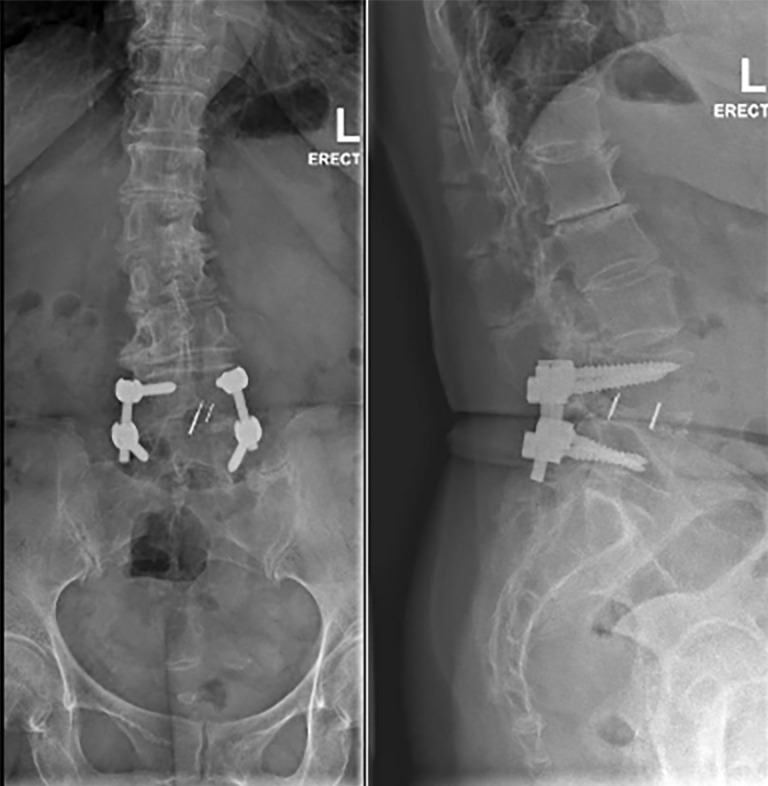

Case description: A 69-year-old woman with a prior L4/L5 TLIF presented to the clinic with a new onset of right lower limb radiculopathy along the L3 dermatome, as well as numbness in the L2 distribution. Magnetic resonance imaging (MRI) studies revealed adjacent segment degeneration in L2/L3 and L3/L4, with disc-osteophyte complexes impinging onto the exiting L2 and L3 nerve roots, respectively. We opted for a right L2/L3 and L3/L4 unilateral endoscopic biportal transforaminal decompression. The surgery was successful, with the patient being discharged from the hospital on postoperative day 1 with minimal pain. Within 2 weeks, the patient described significant improvement in both back pain and radiculopathy, and the numbness had completely resolved. Oswestry Disability Index was used to objectively quantify outcomes and saw an improvement from 15 to 0. Notably, there were no complications.

Conclusions: This case highlights the successful use of unilateral biportal endoscopic transforaminal decompression to treat multi-level ASD of the lumbar spine, instead of the convention and more opted for revision TLIF. Endoscopic spinal surgery provides a promising alternative to other techniques, which can be worth its steep learning curve. This should be considered in the arsenal of spine surgeons as a minimally invasive alternative.